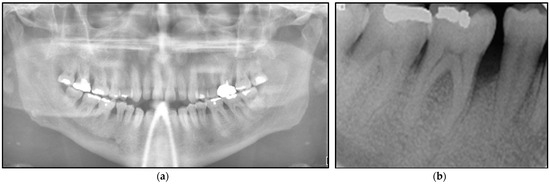

2.2.1. Clinical Examination

2.2.2. Investigations